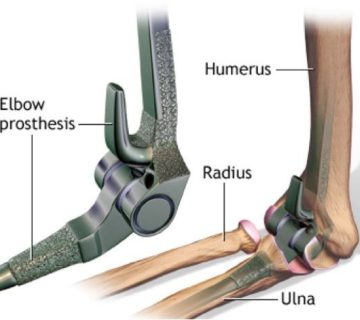

اسکافوئید( Scaphoid ) همراه با بقیه استخوانهای مچ دست یک ساختار استخوانی برای مچ و دست فراهم کنند. این استخوان همراه با استخوانهای لونیت و سطح دیستال رادیوس و اولنا در حرکات مچ اثر میگذارند ( شکل ۳ ) . این استخوان لبه خارجی تونل کارپال را تشکیل داده و با پنج استخوان رادیوس، تراپیزوئید ، تراپیزیوم ، کپتیت و لونیت مفصل میشود . همچنین تکمه آن محلی برای اتصال لیگامان عرضی مچ دست و در مواردی فیبرهایی از عضله ابداکتور پولیسیس برویس است. لیگامان رادیال کلترال به سطح خارجی ان متصل میشود.

( شکل ۳ ) استخوان های مچ دست .